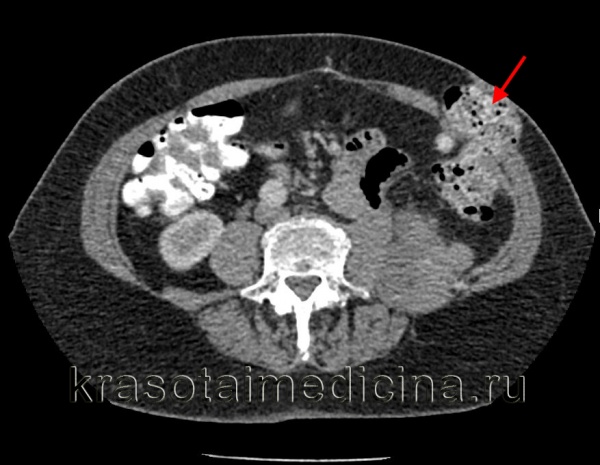

КТ ОБП/ЗП. Дефект передней брюшной стенки с пролабированием петли кишки (красная стрелка) в подкожную клетчатку.

КТ ОБП. Пролабирование петли нисходящей ободочной кишки через боковую стенку живота в подкожную клетчатку.